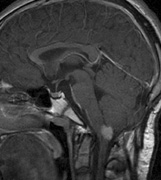

Mental retardation and seizures in TSC are often associated with benign CNS astrocytic hamartomas.131 On imaging, the cerebral lesions show three patterns:132

2. Subependymal nodules (SEN) are typically found along the lateral borders of the ventricles and parehncymal brain lesion (“cortical tubers”) (Figs. 14 and 15). Calcification in the first year of life is rare.132

On MRI imaging, the subependymal nodules and parenchymal brain lesions of infants (age ≤3 months) and adults show different signal characteristics. Infant CNS tubers are hyperintense on T1-weighted images and hypointense on T2-weighted images, which is the opposite of the pattern seen in adults.134 Malignant transformation of SEN occurs in about 10% to 15% of patients and the resultant subependymal giant cell astrocytoma accounts for 25% of premature deaths in TSC.135,136

Fig. 14. Tuberous Sclerosis Complex: Sub-Ependymal nodules. These are typically found along the lateral borders of the ventricles.132

Fig. 15. Tuberous Sclerosis Complex. (a) Patient 1: Axial CT scans demonstrating typical calcification of subependymal nodules in a 13-year-old girl with a history of seizures. (b and c) Patient 2. (b) Axial T2-weighted images demonstrate calcified subependymal nodules (arrowheads) and cortical tubers typical of tuberous sclerosis. (c) Widespread cortical tubers are seen on a coronal FLAIR sequence as thickening of the cortex and high signal of the subcortical white matter.